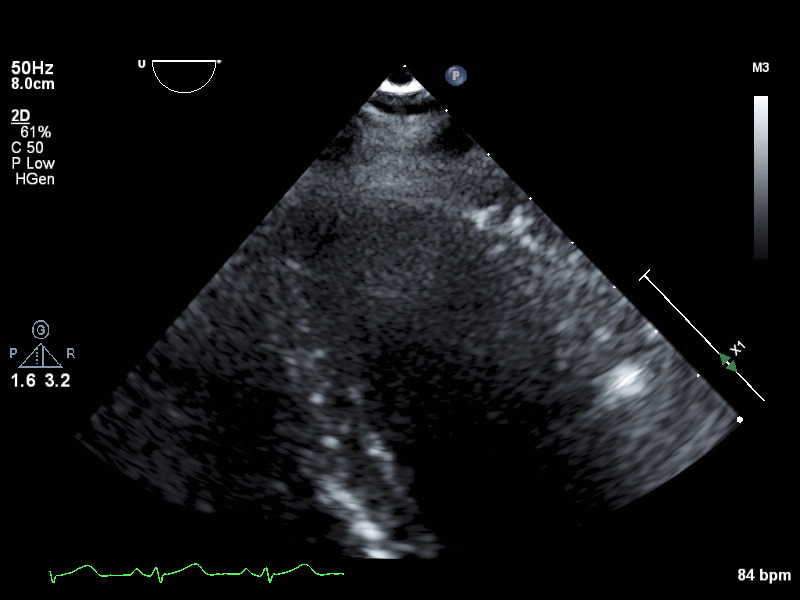

Subcostal & Suprasternal (3 views)

ImageView NameDescription

subcostal-heart subcostal-heart Subcostal window, focused on the heart

subcostal-ivc subcostal-ivc Subcostal window, focused on the inferior vena cava

suprasternal suprasternal Suprasternal view